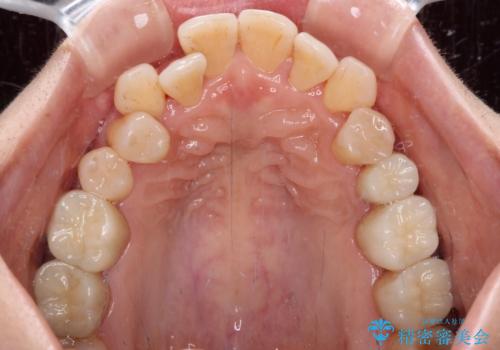

銀歯を白くしたい セラミックによる審美歯科治療

知覚過敏の症状はなくなり、希望通りの白い歯になったと、患者様は大変満足されました。